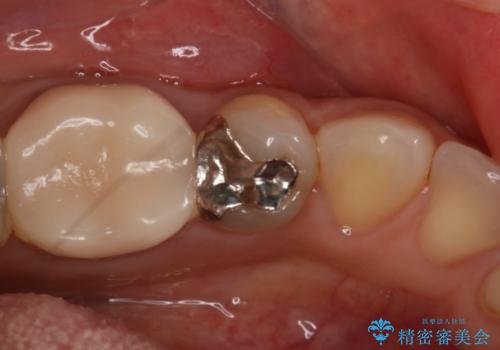

- 左下5番の銀歯をセラミックにやり変え希望の患者様です。

切削量を考慮し、セラミックインレーでの治療を選択しました。

銀歯直下のう蝕を除去しCRで裏層を行った上で、形成・印象を行っています。